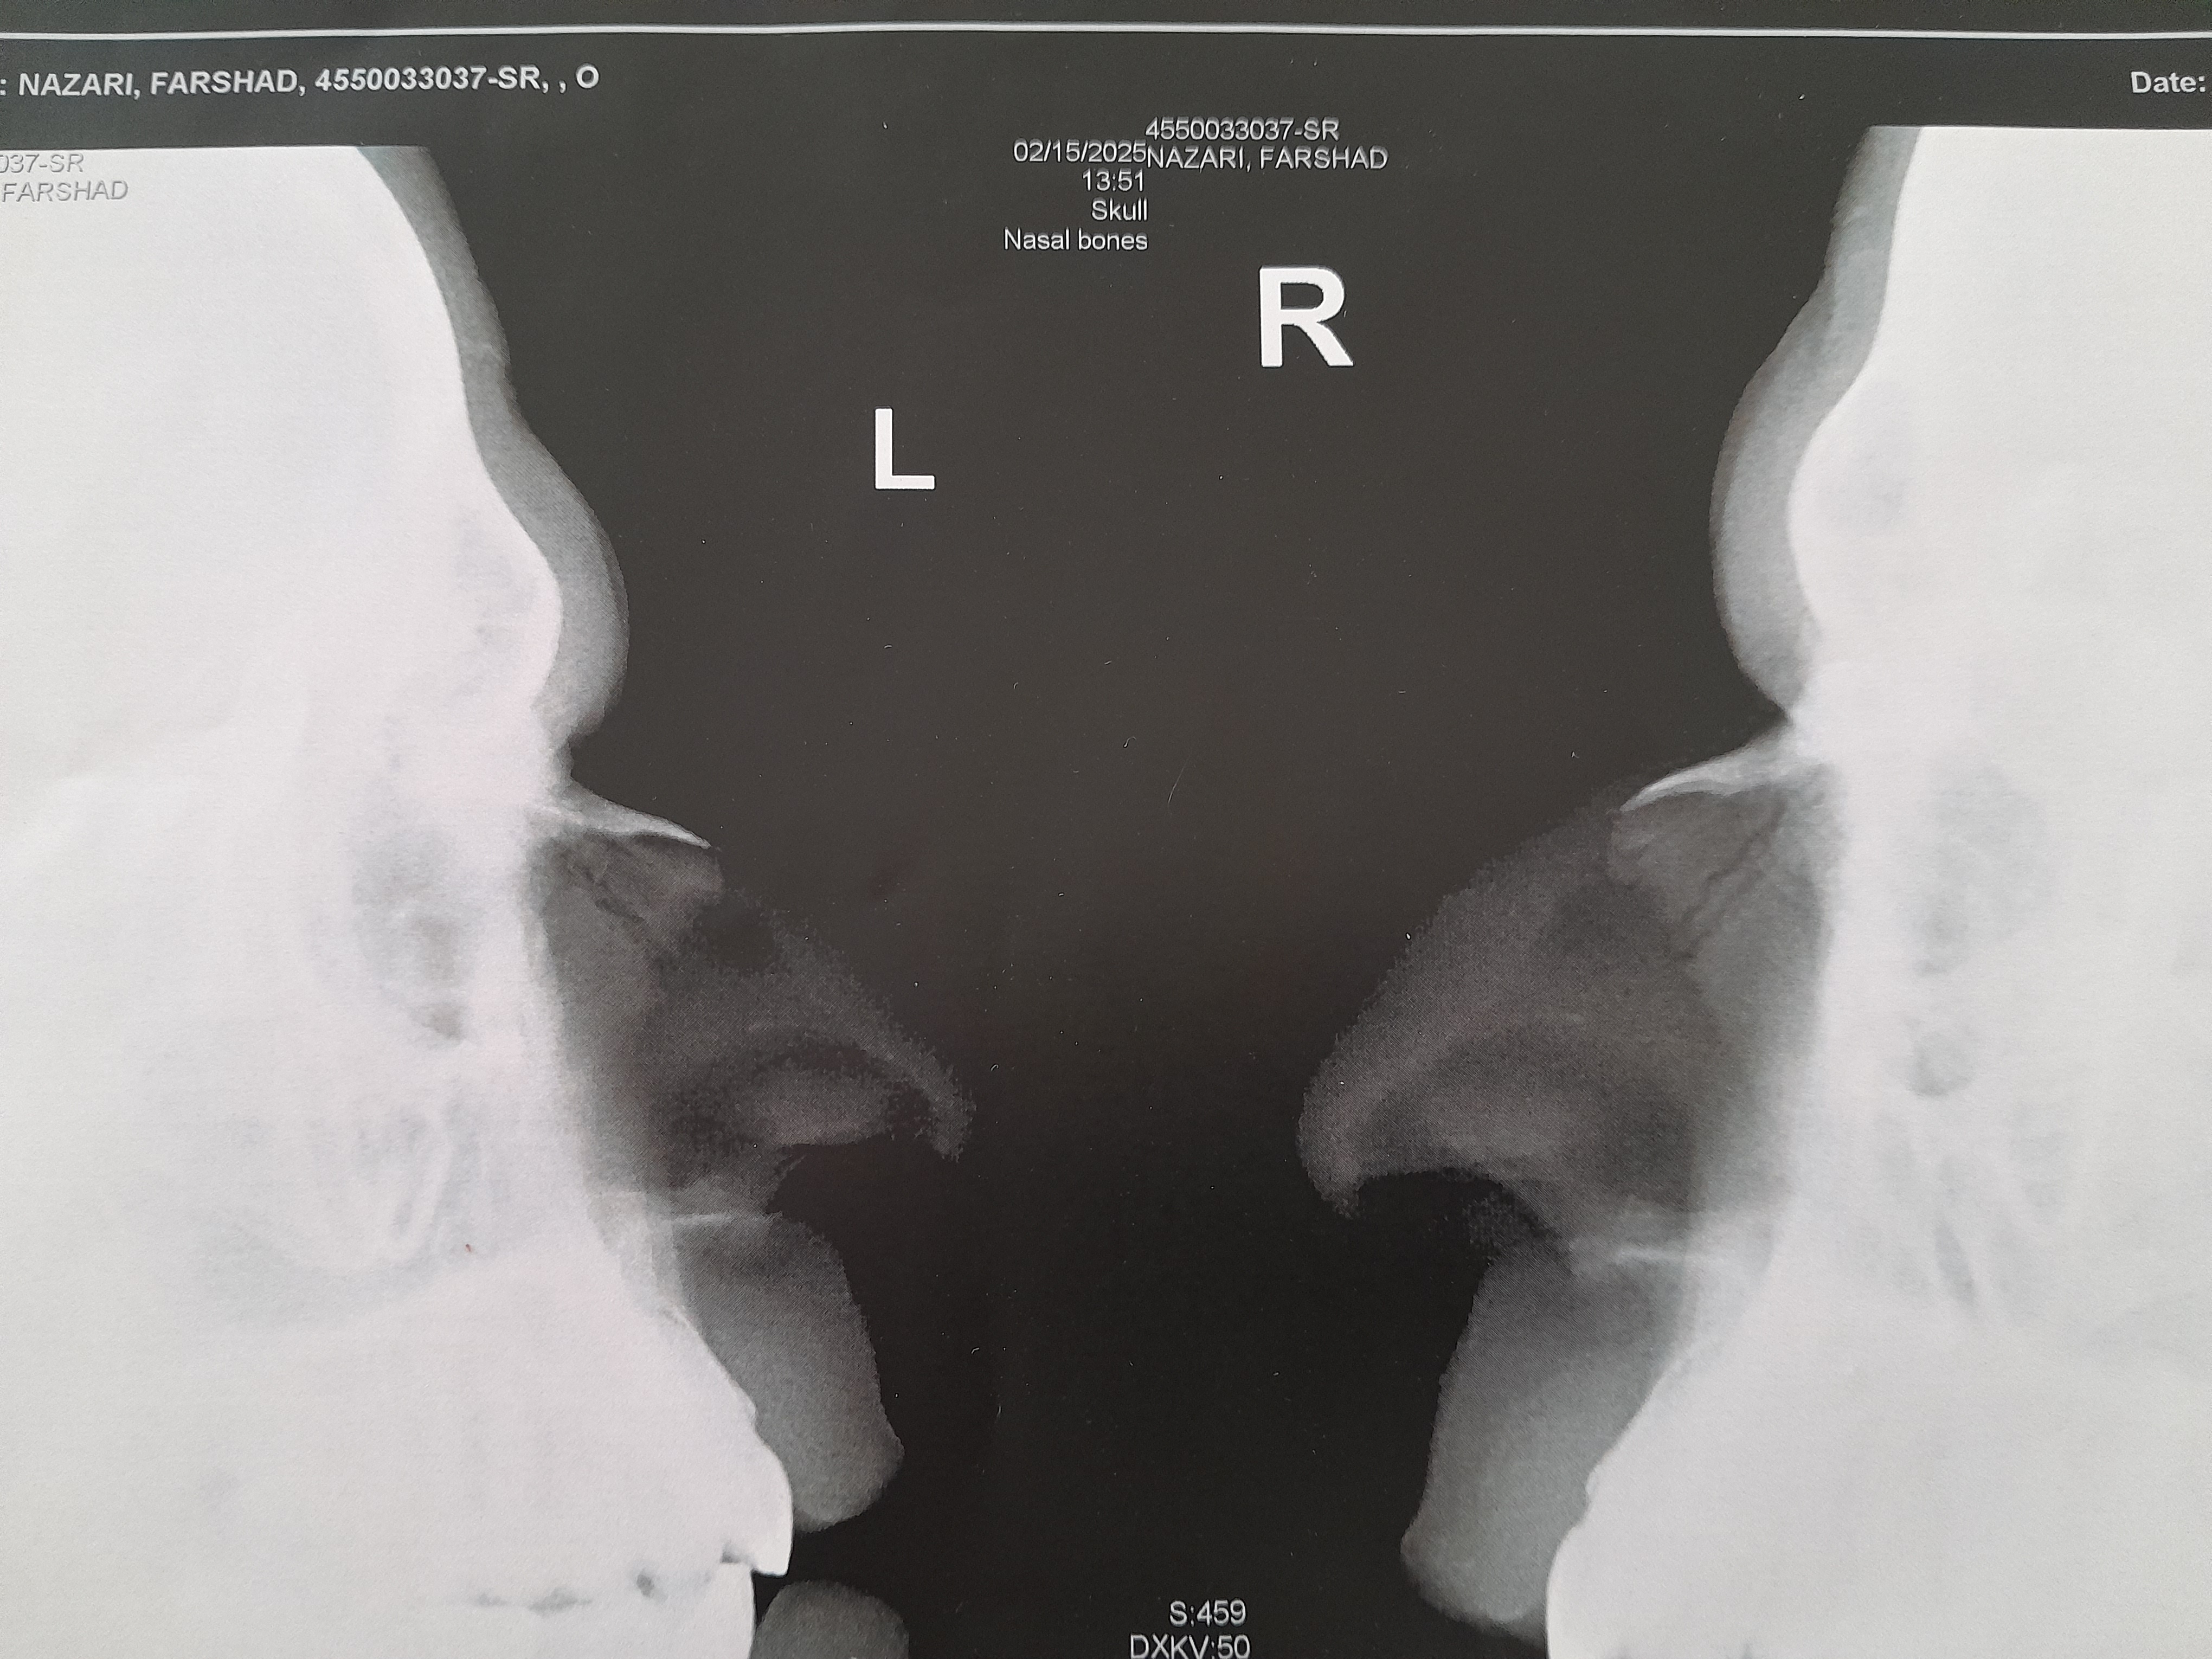

اگ شکسته فک کنم گچ بگیرن اوک شه

من خودم بینیم شکسته بود ده سال پیش سر سری گرفتم همونجوری جوش خورد

امسال عمل کردم